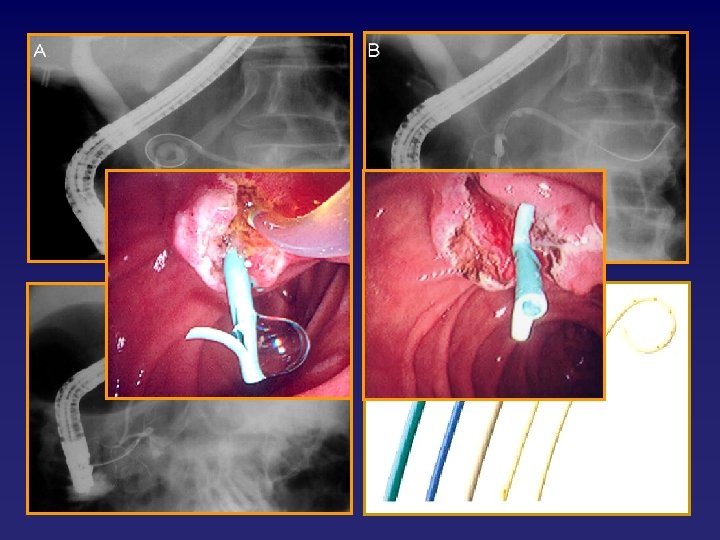

ERCP sonrası pankreatitin önlenmesinde endoskopik teknikler • Sfinkterotominin pure-cut akım kullanılarak yapılması • Pankreatik stent

Pankreatik stentin pankreatit gelişme riskini azalttığı durumlar • • • • OSD da biliyer sfinkterotomi Pankreatik kanala kontrast enjeksiyonu yapılmadan Biliyer balon dilatasyonu biliyer kanülasyon ve/veya kontrast enjeksiyonu yapılan olgular sfinkterotomi Pankreatik manometrik bulguları normal olan OSD lu Precut sfinkterotomi hastalarda(access) biliyer sfinkterotomi yapılması 60 yaşkanülasyon üzerindeki hastalar Güç Ampullektomi sonrasında pankreatik orfisin rahatça Ampullektomi görülebildiği olgular Pankreatik fırça sitolojisi Freeman ML Gastrointest Endosc 2001

ERCP sonrası pankreatitin önlenmesinde pankreatik stent Otör Protokol Hastalar n Pankreatit Stent - / Stent + p Smithline, 1993 RCT Precut ES, OSD 93 18 / 14 0. 299 Sherman, 1996 RCT Precut ES 93 21 / 2 0. 036 Tarnasky, 1998 RCT Biliyer ES, OSD 80 26 / 7 0. 03 Elton, 1998 Retrspkt Pankreatik ES Tüm endkasyonlar 194 12, 5 / 0, 7 < 0. 003 Patel, 1999 RCT Pankreatik ES, OSD 36 33 / 11 > 0. 05 Vandervoort, 1999 Retrspkt Pankretik fırça sitolojisi 42 28, 1 / 0 0. 08 Aizava, 2001 Retrspkt Biliyer balon dilatasyonu 40 6 / 0 0. 11 Fogel, 2002 Retrspkt Bil. ve pank. ES, OSD 435 28, 2 / 13, 5 <0. 05 Norton, 2002 Retrspkt Endoskopik ampullektomi 28 11, 1 / 20 >0. 05 Fazel, 2003 RCT Güç kanülasyon, biliyer ES, OSD 76 28 / 5 <0. 05 Freman, 2004 Retrspkt Yüksek riskli hasta gurubunda terapötik ERCP 225 66, 7 / 14, 4 0. 06 Catalano, 2004 Retrspkt Endoskopik ampullektomi 103 16, 7 / 3, 3 0. 01 RCT: Randomised controlled trial, ES: Endoskopik sfinkterotomil Freeman ML. JOP 2004